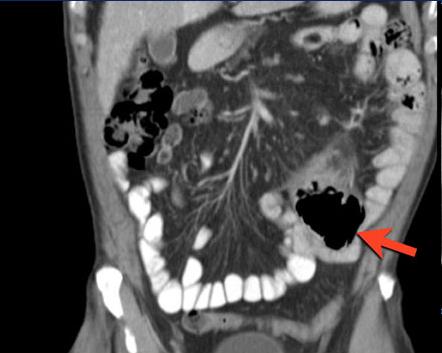

Image TDM en coupe

coronale : Tumeur addeno carcinoma du jejunum

proximale a extension ganglionaire ( fleche rouge )

. Dilatation du jejunum en amont et aval . |

| |